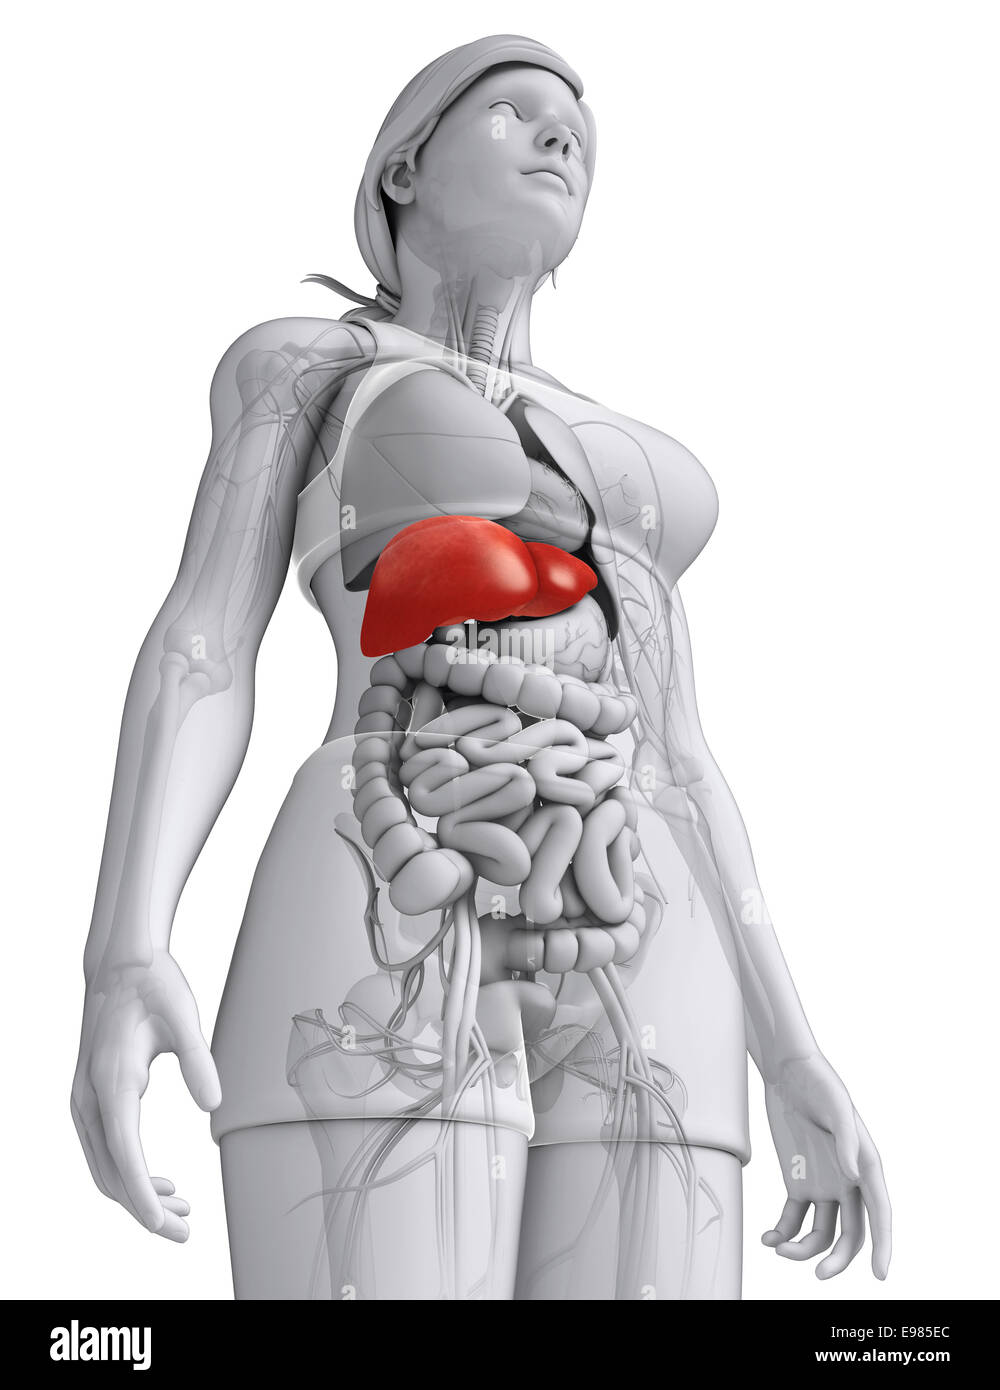

Физиология беременности: строение органов